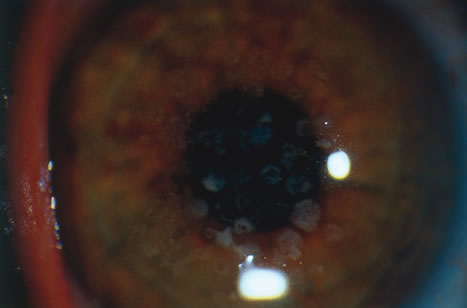

Meesmann's Dystrophy

Meesmann's dystrophy consists of tiny, fine cystlike structures accumulating within corneal epithelial cells, giving the anterior surface of the cornea a multiple oil-droplet appearance (Fig. 25). The lesions are entirely intraepithelial. Although the abnormality usually is manifest in the first decade of life, the degree of cyst formation is relatively stable. This epithelial abnormality generally does not cause decreased vision to more than 20/40. The cysts may rupture at the surface, leading to a foreign body sensation.

Fig. 25. Meesmann's corneal dystrophy. The characteristic slit lamp appearance is best demonstrated either by retroillumination (A) or through a red reflex (B). The latter best shows the increased distribution of tiny droplet-like lesions in the central cornea.

Histopathologically, numerous tiny intraepithelial cysts are seen, which result from the dissolution of the normal tonofibrillar skeleton of the epithelial cells.126,127 The full thickness of the epithelium is affected, with even the basal cells showing diffuse abnormalities. The matrix of the tonofibrils is composed of an abnormal complex containing a glycoprotein acid mucopolysaccharide compound that contains glycogen. Meesmann's corneal dystrophy is caused by mutations in the genes for cornea-specific cytokeratins K3 or K12.128,129